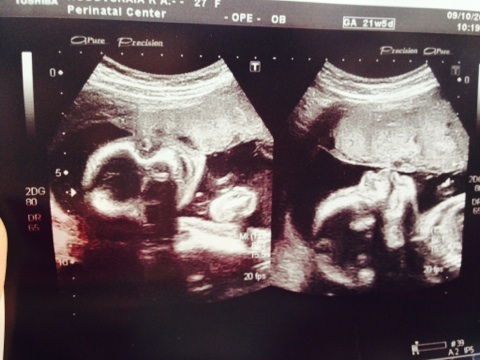

Позади 22 недели... (Фото)

Клевый пуз))) и сыночек прям писюны уже такая)))))))))

Дааа))) писюн прям вышел хорошо на фото)))